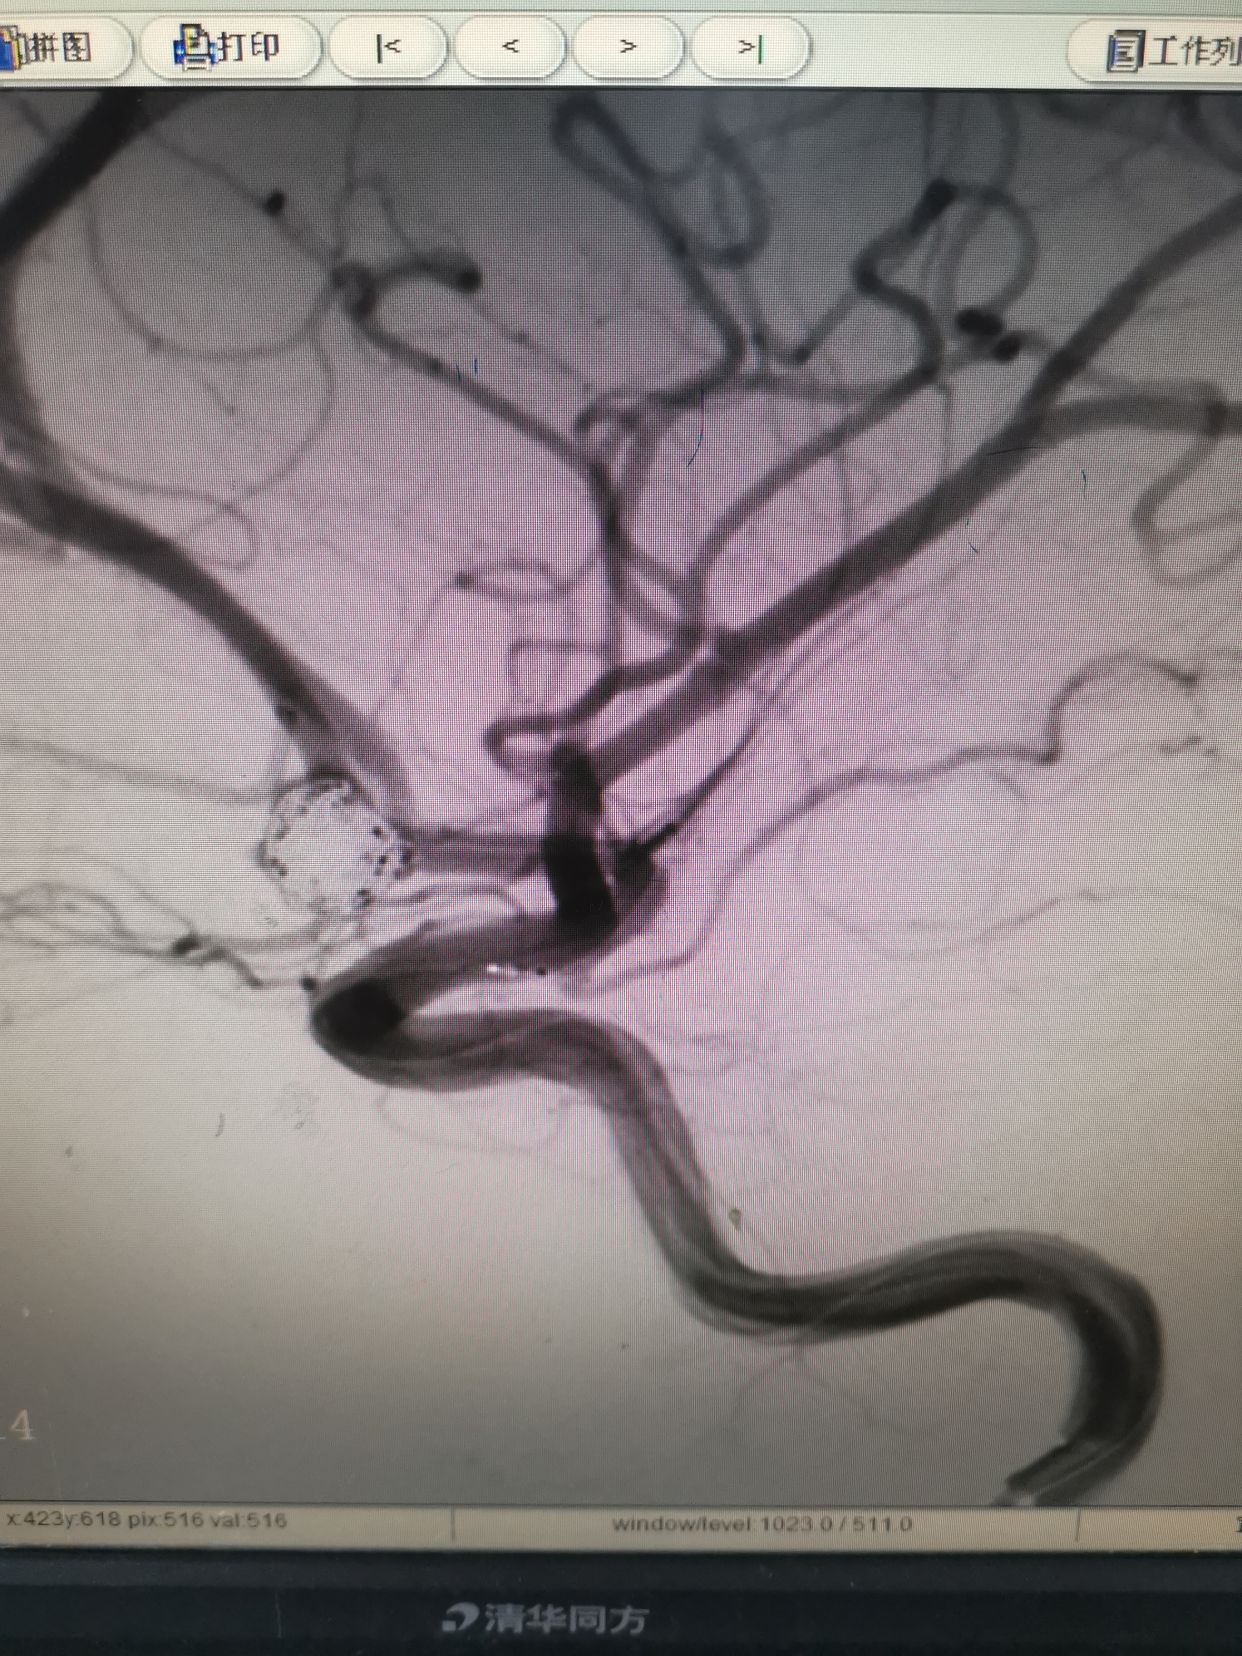

左侧颈内动脉造影,发现一宽颈前交通动脉瘤。